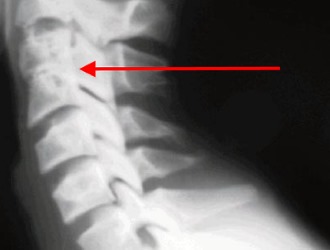

При конкресценции шейных позвонков наблюдается их слияние.

- Рентгенографию, которая помогает определить участки сращения позвонков;